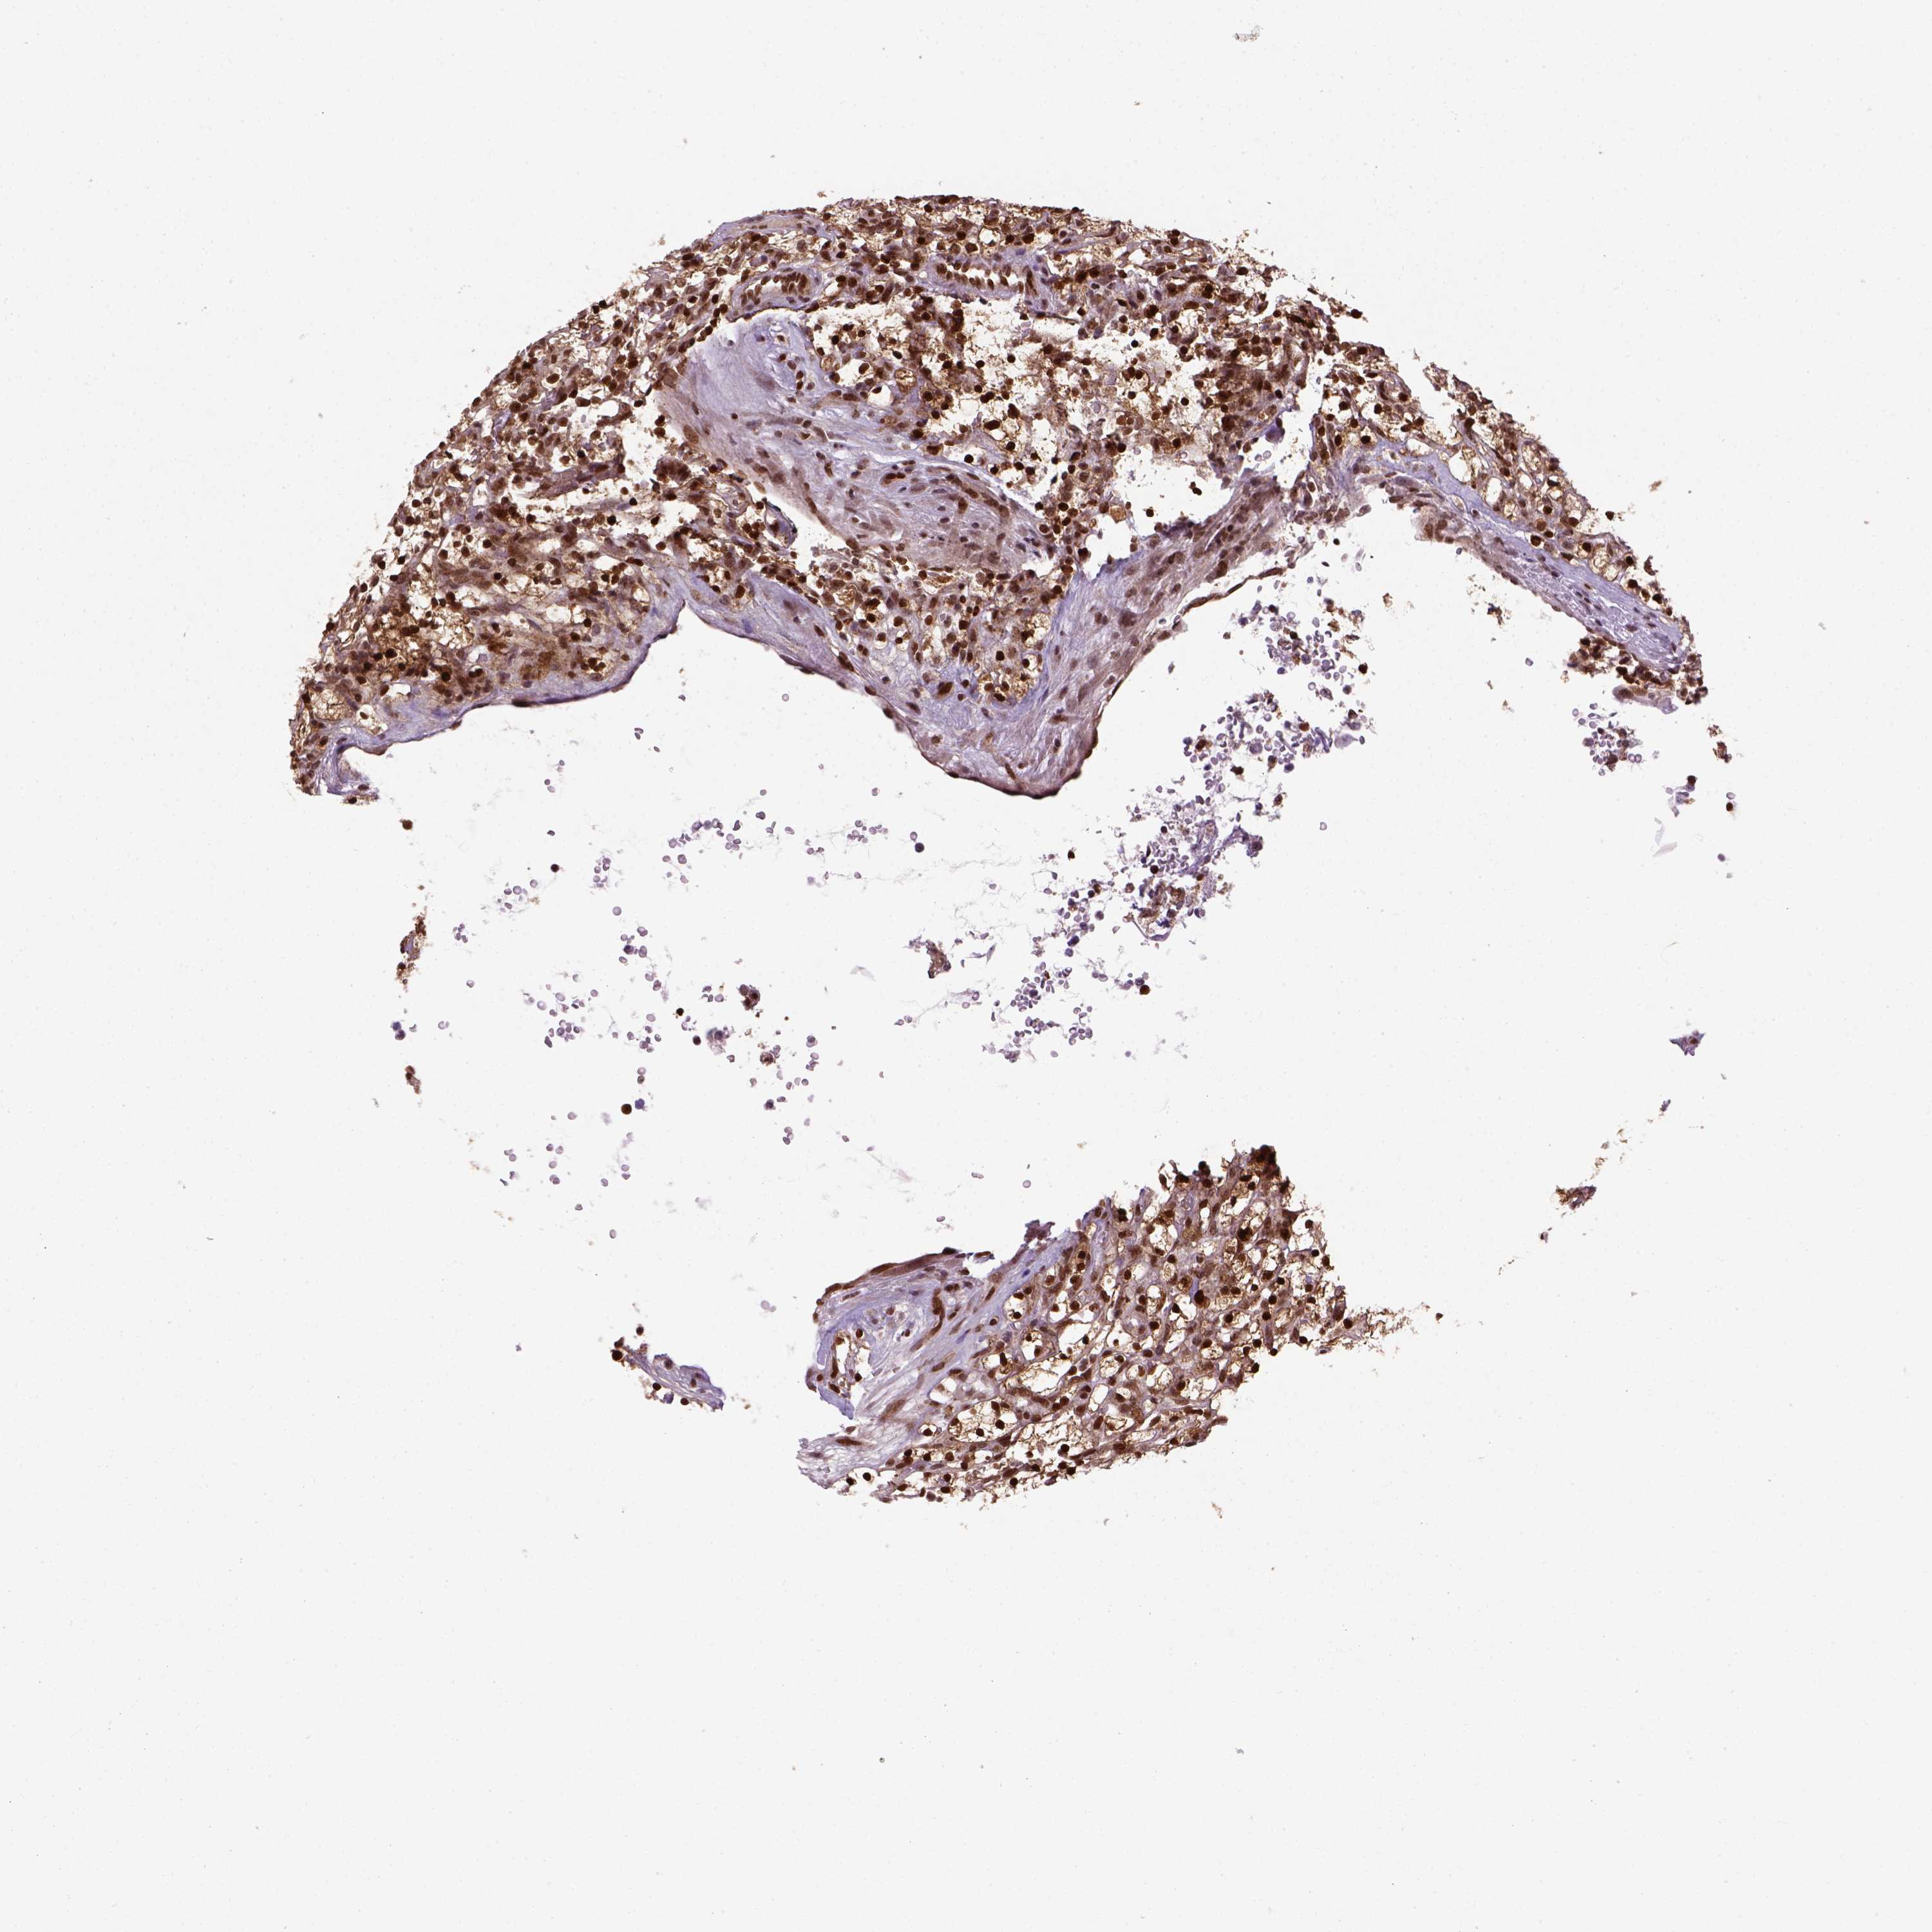

MGMT